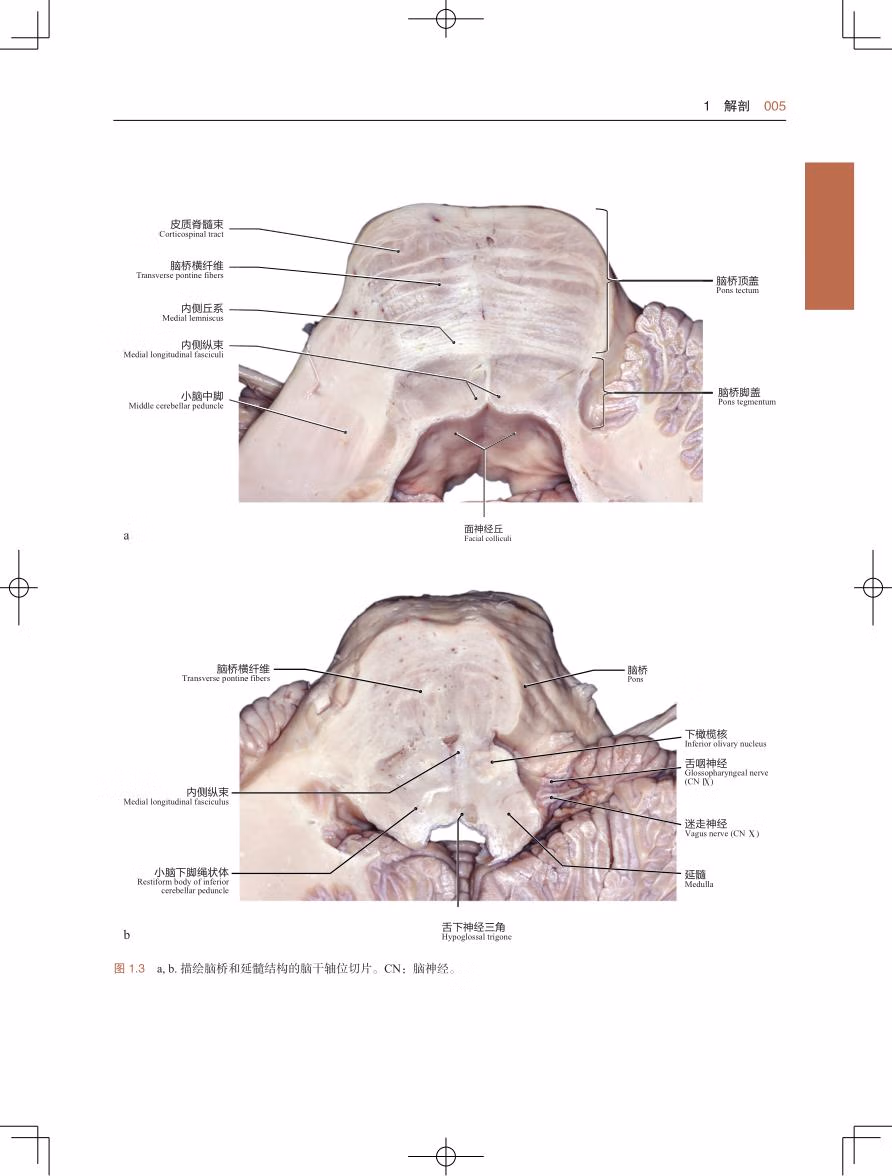

本书为国际神经外科 专家合著的关于脑干解剖及外科手术的图谱,详细介绍了脑干的神经解剖及在脑干手术中相对安全的入路,总结了脑干手术的原则及对脑干、丘脑、松果体等部位病损的手术入路解剖,同时列举了大量脑干手术的临床病例。本书以图为主,辅以简明扼要的文字解说,同时配合大量解剖绘图、病例影像学图片、手术图片(合计1 700 余幅)及视频(51 部)和动画(7 个),使读者能更好地掌握脑干手术的操作技巧。本书适合国内各级神经外科及相关科室临床医生阅读。